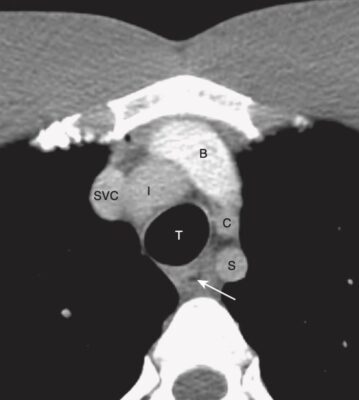

Mức 5 mạch máu (Hình 5)

- Ở mức này, có thể xác định được hai phổi, khí quản (T) và thực quản. Khí quản có màu đen vì chứa không khí; thường có hình bầu dục và đường kính khoảng 2 cm. Thực quản nằm phía sau và ở bên trái hoặc bên phải của khí quản. Nó thường xẹp nhưng có thể chứa không khí nuốt vào.

- Tùy thuộc vào mức của lát cắt, có thể thấy một vài mạch máu lớn. Các cấu trúc tĩnh mạch có xu hướng nằm ở phía trước so với động mạch.

- Các tĩnh mạch cánh tay đầu (brachiocephalic veins, B) nằm ngay sau xương ức. Từ bên phải của bệnh nhân sang bên trái, các động mạch có thể nhìn thấy được có thể bao gồm động mạch vô danh (innominate, I), động mạch cảnh chung trái (C) và động mạch dưới đòn trái (S).